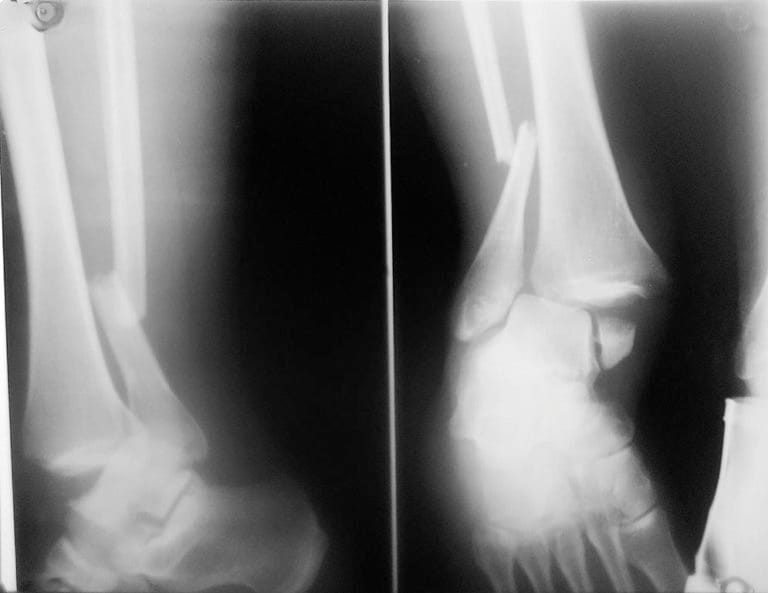

Мультяшные сломанные кости: Рисунки и комиксы

Раздел: Фотоархив